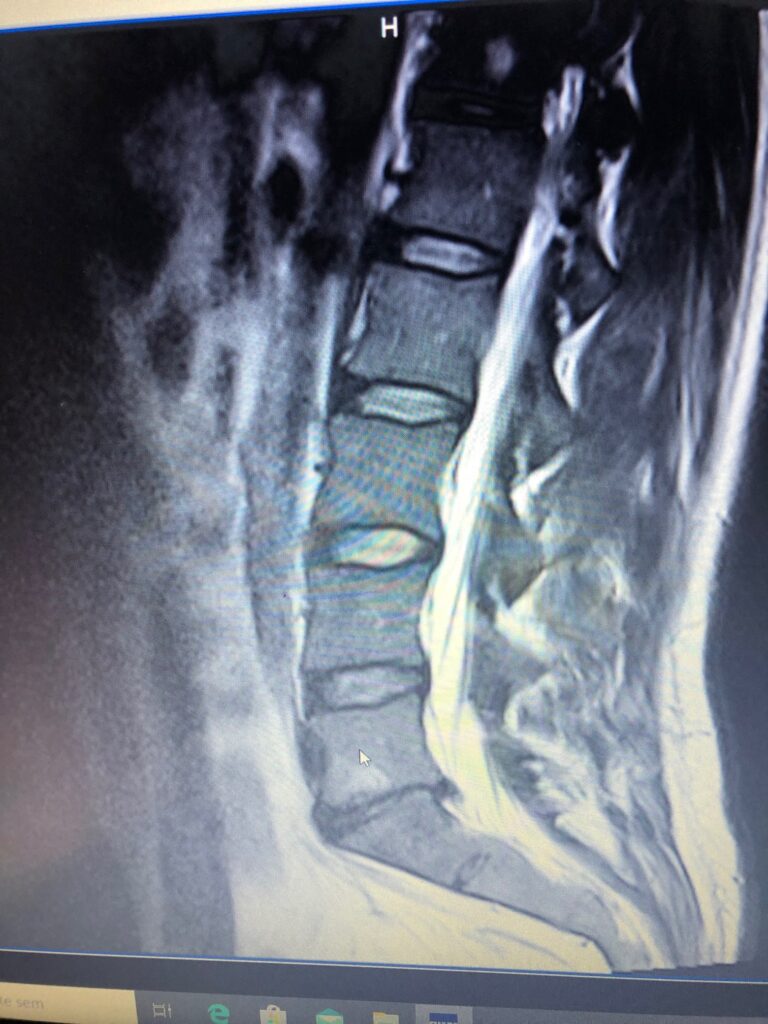

Disc Herniation L5-S1